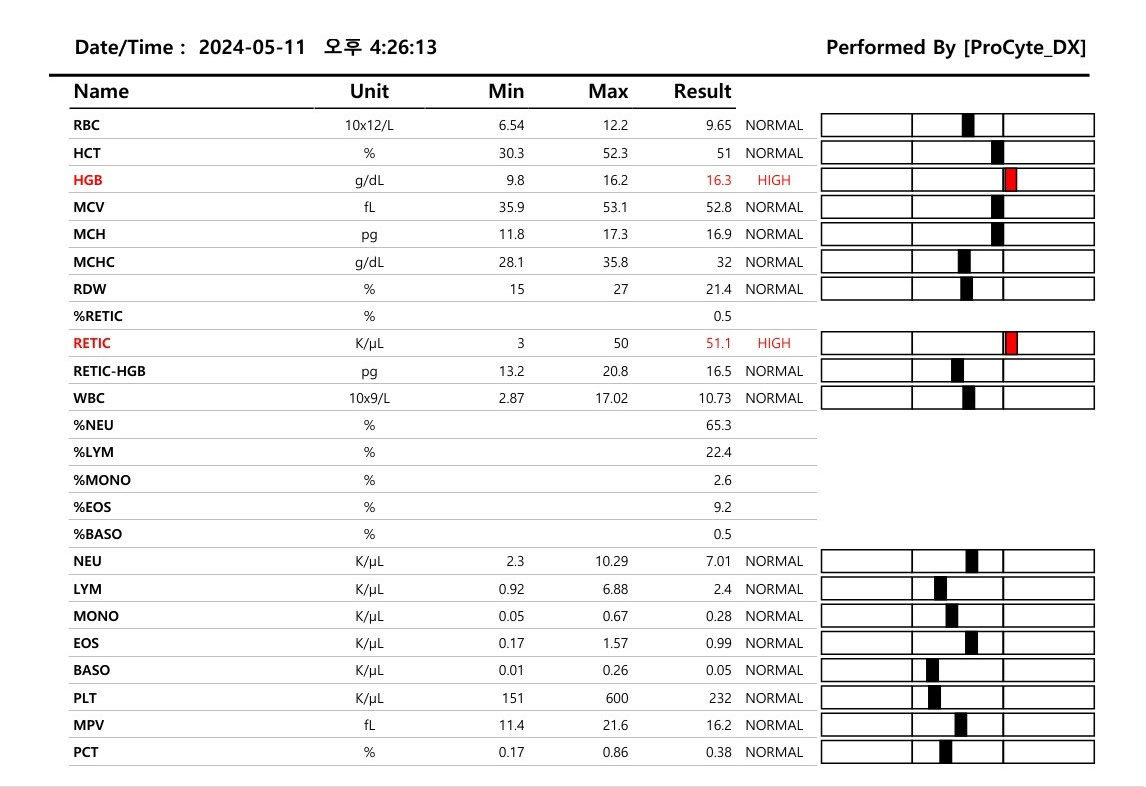

음... 이 날은 기본적인 혈액검사랑

예전 건강검진 때 살짝 좋지 않았던 부분을

중심으로 검사를 진행하기로 했다.

혈액검사, 간기능검사, 신장기능검사,

SDMA신부전조기검사를 했고

정밀복부초음파를 진행했다.

혈액검사결과는 좋다고 하셨다!